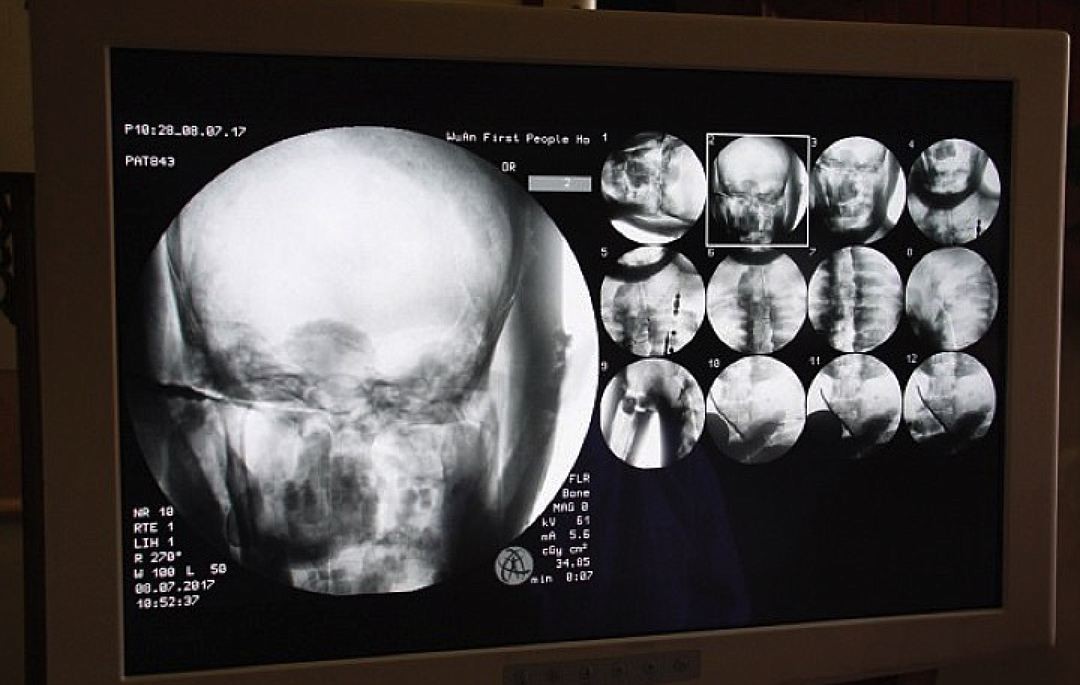

Что двигало монахами, неизвестно — возможно, любопытство. Мол, что там внутри? Но медики охотно согласились. Недавно - 8 июля 2017 года — они привезли в храм аппаратуру и сделали мумии компьютерную томографию. Шокированы были все — и медики, и монахи, и журналисты, и паломники, собравшиеся поглазеть на исследования. Томография выявила, что кости, суставы и зубы у 1000-летнего Цы Сяня как у живого. Неизменным сохранился и мозг.

- Невероятное зрелище! - так охарактеризовал увиденное доктор У Юнцин (Dr Wu Yongqing), проводивший сканирование.